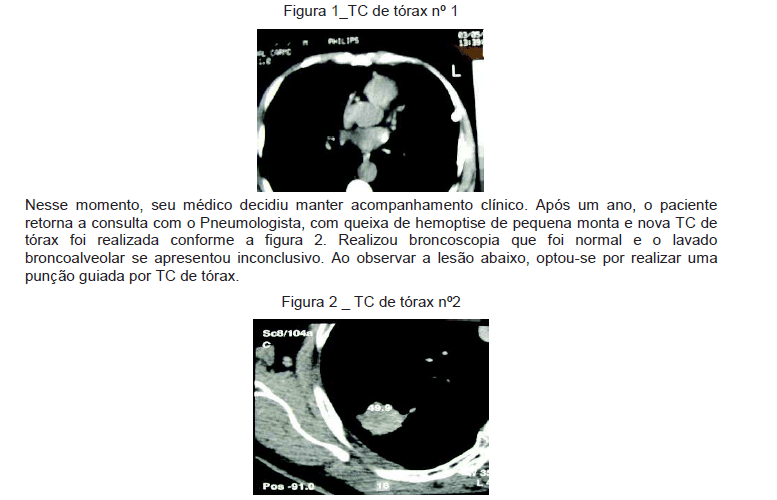

Homem de 75 anos, há 20 anos com tosse seca, sibilância e dispneia progressiva. Ocasionalmente tem tosse produtiva com expectoração mucóide. Em uso de aerossol com a associação salbutamol e ipratrópio. Ex-fumante há três anos, tendo fumado dos 12 aos 72 anos de idade (90 anos/maço), pai falecido com câncer gástrico. Realizou a TC de tórax nº 1, conforme figura 1.

Em relação às TC de tórax apresentadas nas figuras 1 e 2, é correto afirmar que